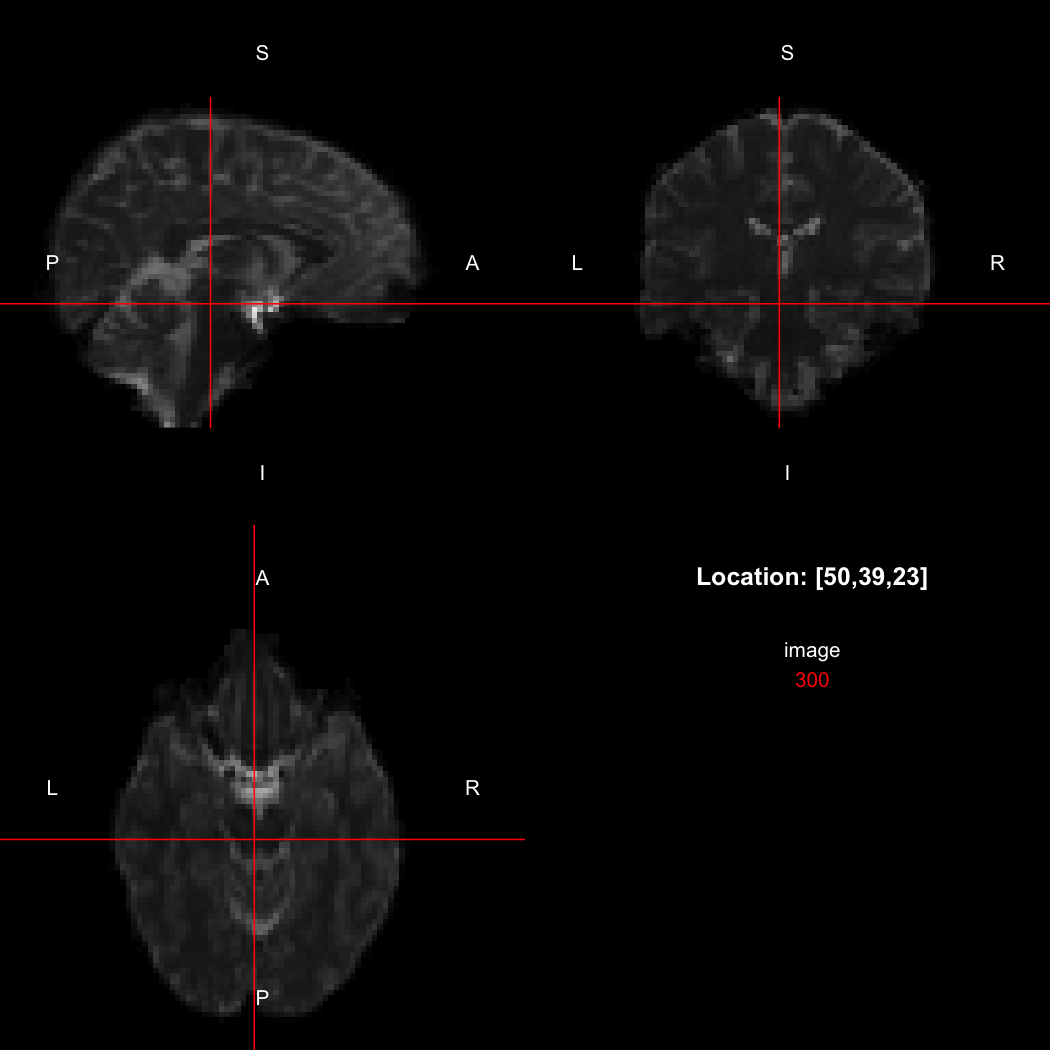

The package contains a basic image viewer, which can be used interactively or noninteractively to examine 2D or 3D images.

view(image)

By default, the viewer shows labels indicating image orientation, crosshairs pinpointing

the currently selected location, the numerical indices of the current

location, and the value of the image at that location. Options allow

each of these to be turned off, for the content of the bottom-right

panel to be customised entirely, for the colour scale to be changed, and

for additional images to be layered on top of the base image. See

?view for details.

## [1] "LAS"So, here, “LAS” means that the positive x-axis points left, the positive y-axis anterior and the positive z-axis superior. This is the so-called “radiological” orientation convention, and can be requested when viewing images for those who are used to it:

view(image, radiological=TRUE)

Notice the left (L) and right (R) labels, relative to the view shown

above. Setting the radiologicalView option to

TRUE will make this the default for all future views.